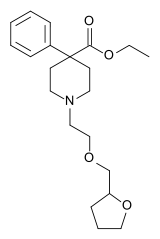

Pirinitramides

Structures

| Pirinitramides | ||||

|---|---|---|---|---|

|

| |||